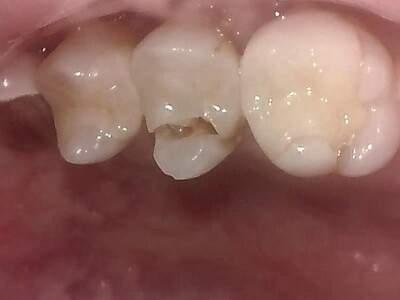

歯冠破折

歯冠(歯の頭の部分)のみ欠けることです。

歯根(歯の根っこの部分)まで破折が診られない場合は欠けた部分を除去し、詰め物や被せ物で修復します。

歯が大きく欠けた場合、神経まで刺激が到達することで痛みが出ることがあり、根管治療を必要とすることもあります。